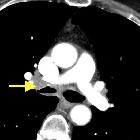

CT

May show mucosal thickening +/- calcification involving segments of the trachea and bronchi. The affected portions of the airway can also be narrowed.

When it involves the trachea, the posterior membrane is also classically involved . CT is also considered to be useful in assessing the extra-luminal extent of disease .